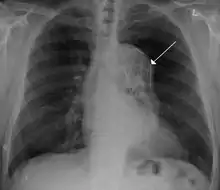

A thoracic aortic aneurysm is an aortic aneurysm that presents primarily in the thorax.

A thoracic aortic aneurysm is the "ballooning" of the upper aspect of the aorta, above the diaphragm. Untreated or unrecognized they can be fatal due to dissection or "popping" of the aneurysm leading to nearly instant death. Thoracic aneurysms are less common than an abdominal aortic aneurysm.[2] However, a syphilitic aneurysm is more likely to be a thoracic aortic aneurysm than an abdominal aortic aneurysm. This condition is commonly treated via a specialized multidisciplinary approach with both vascular surgeons and cardiac surgeons.